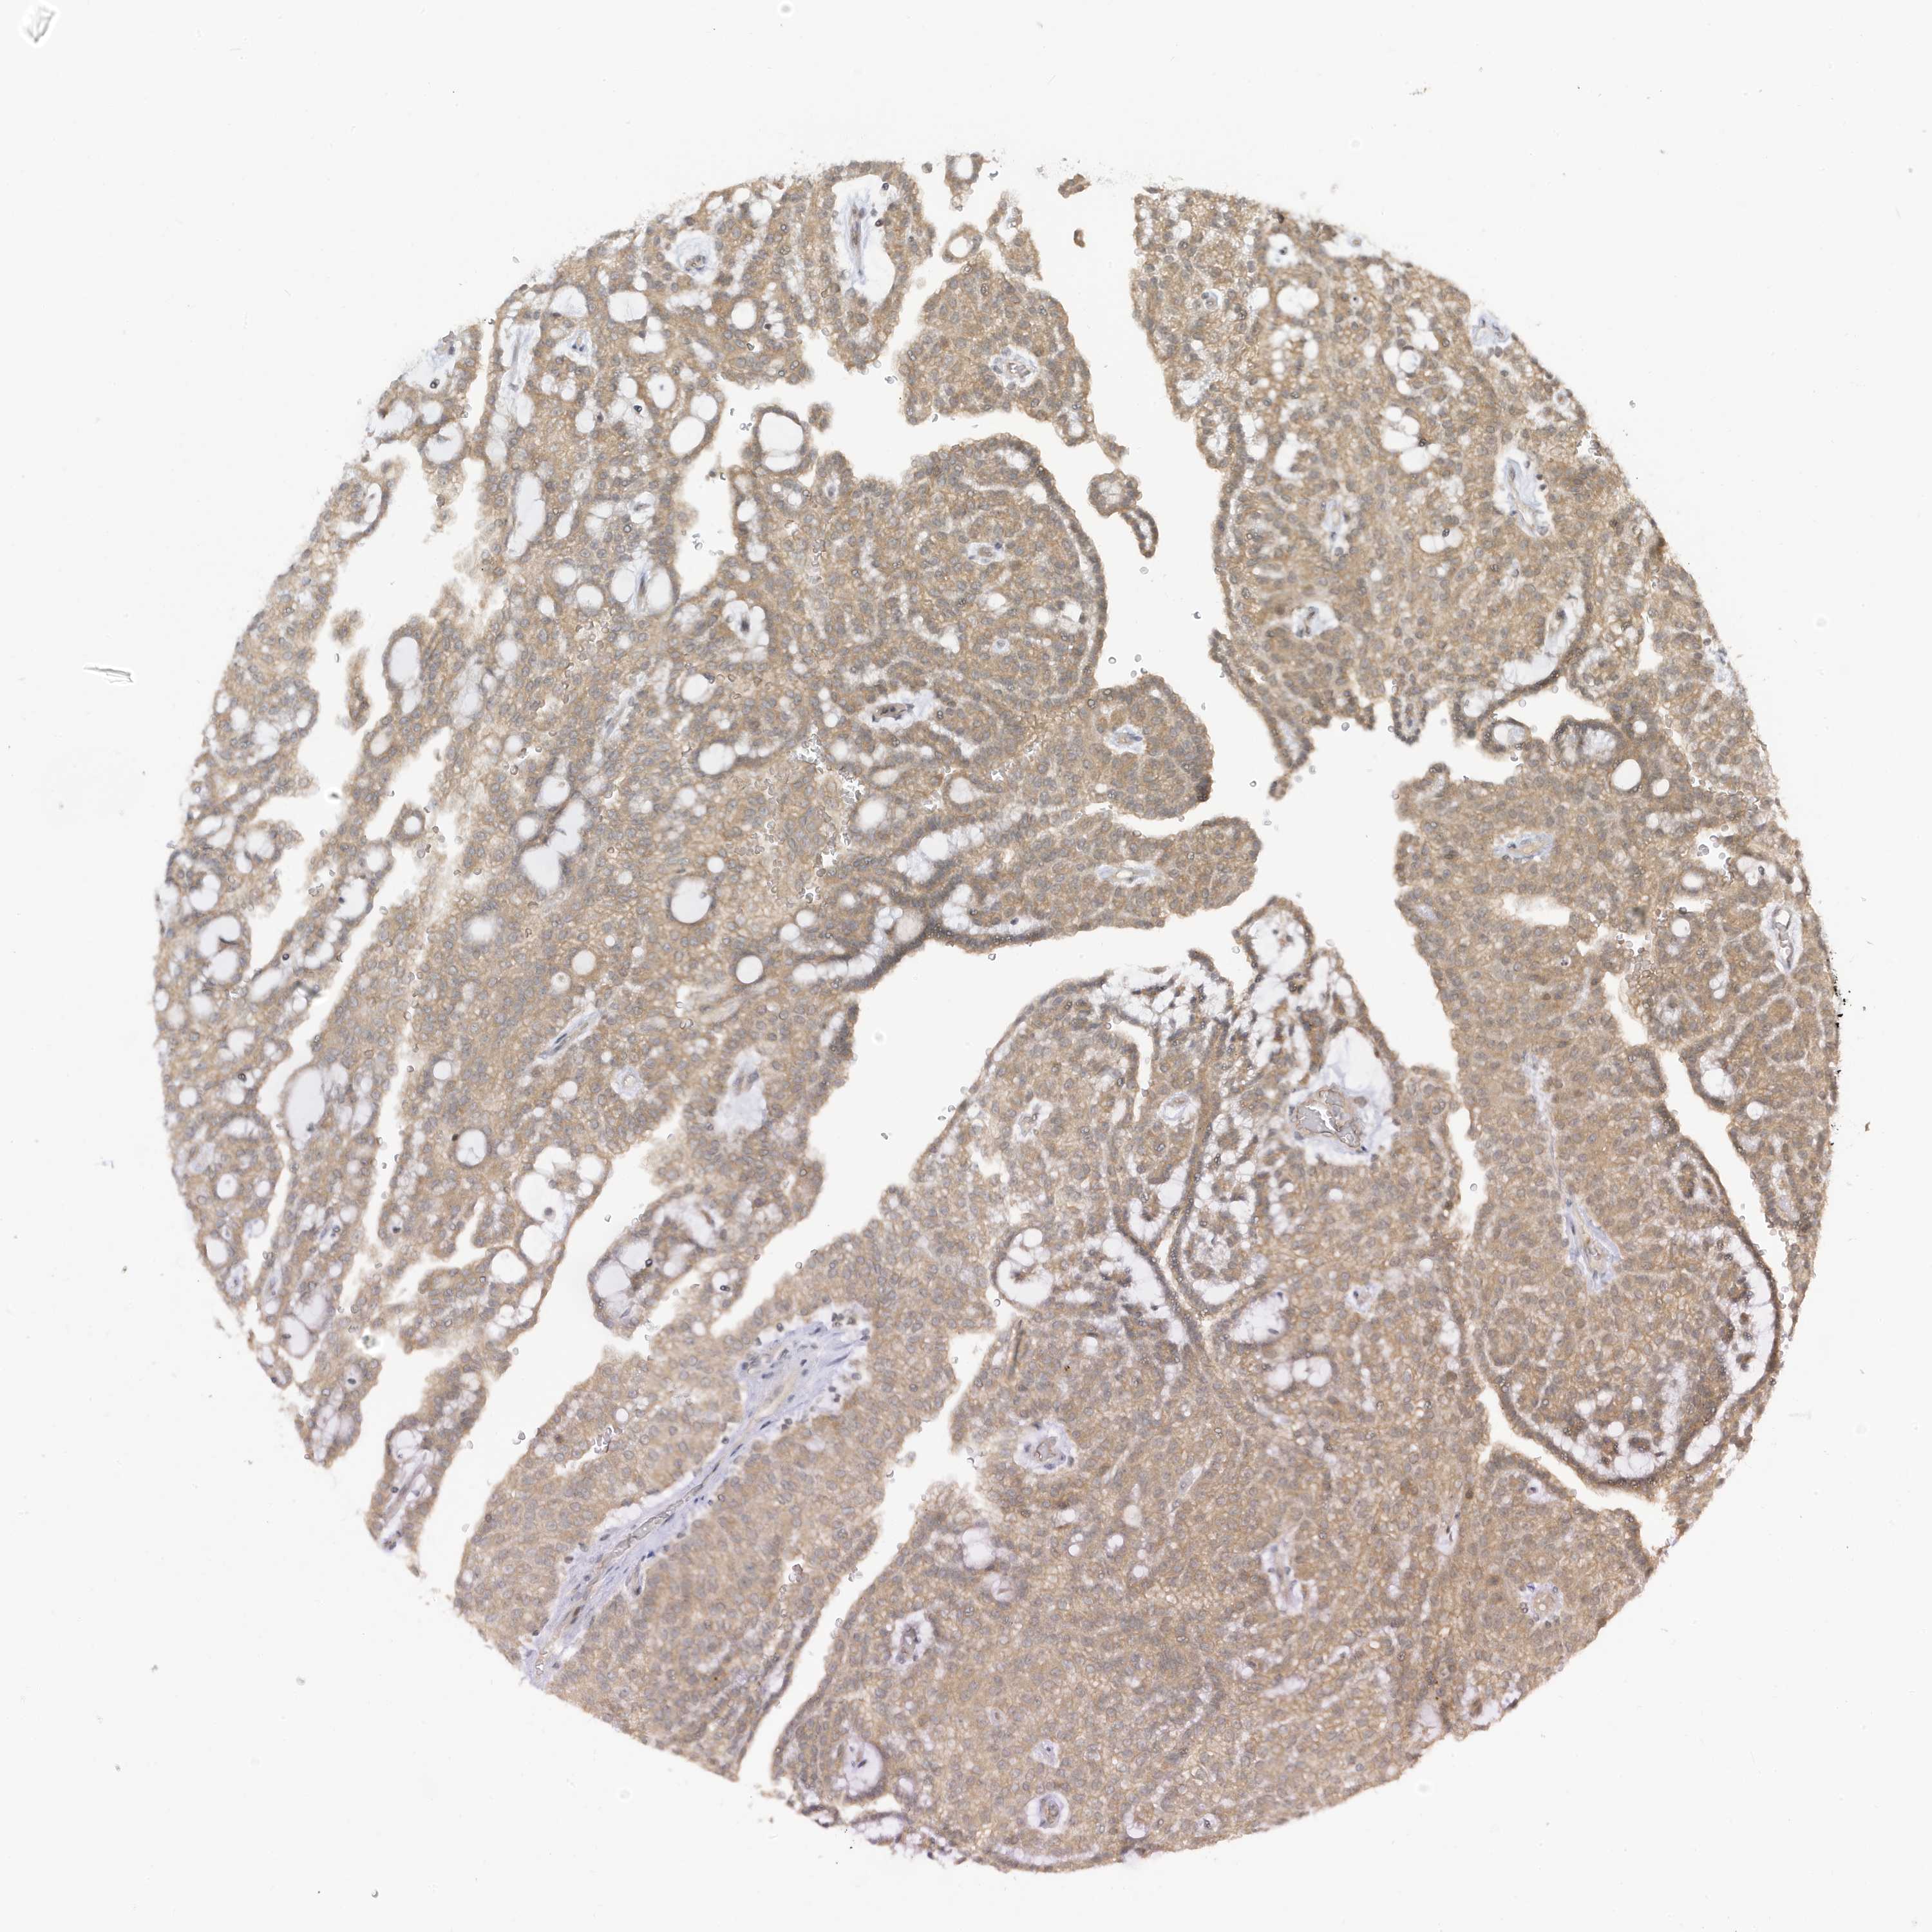

KIDNEY RENAL CLEAR CELL CARCINOMA (VALIDATION) - Interactive survival scatter ploti

TAB3 is not prognostic in Kidney Renal Clear Cell Carcinoma (validation)

: 12.66

Average pTPM 15.9

Number of samples 100